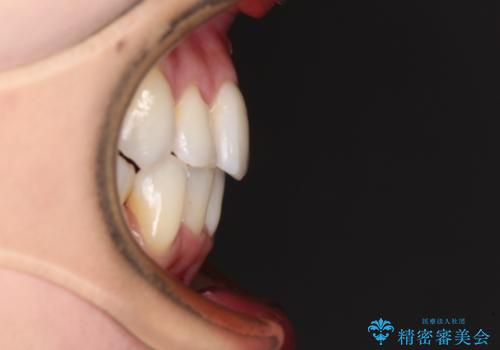

- 結婚式に向けて、八重歯と虫歯で変色した歯を改善したいとのことで来院された患者様です。

上下ともにデコボコが強いため、上下顎左右小臼歯各1歯を抜歯して歯列を整えることとしました。

大きな虫歯が認められた歯は、矯正治療後にオールセラミッククラウンにて補綴治療を行うこととしました。